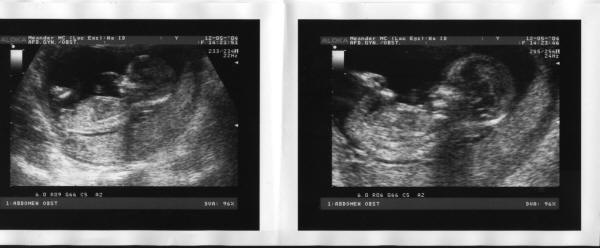

De echo

Deze echo is gemaakt op 12 mei 2004. Je kunt al heel goed zien dat er een echt 'mensje' in de maak is.